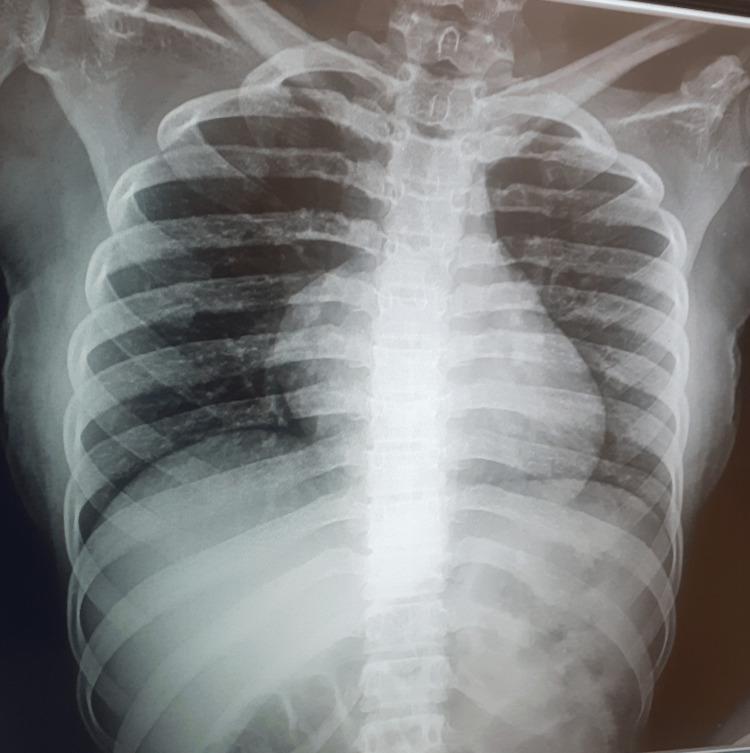

Fahr's syndrome is a rare, progressive, neuropsychiatric disorder characterized by bilateral and symmetrical calcifications over the basal ganglia and other parts of the brain, leading to a wide range of clinical manifestations ranging from neurologic symptoms of movement disorders, seizures, and cerebellar dysfunction to neuropsychiatric symptoms such as dementia, psychosis, and mood disorders. The widespread calcific deposits within the brain tissue that characterize Fahr's syndrome develop secondary to different underlying conditions such as parathyroid disorders, brain infections, and toxic exposures. Hypoparathyroidism, a rare disorder of calcium and phosphate metabolism, is the most commonly identified etiology of Fahr's syndrome. In this case, we report a case of a 17-year-old female patient who presented with status epilepticus. Her past medical history was positive for intermittent episodes of generalized tonic-clonic seizures for the past year. Upon presentation, she had a decreased level of consciousness with a Glasgow Coma Scale score of 9 (eye-opening = 2, verbal response = 2, motor response = 5). Chvostek's and Trousseau's signs were positive. Initial laboratory workup revealed severe hypocalcemia, hyperphosphatemia, and markedly low parathyroid hormone levels. Computed tomography of the brain showed extensive, bilateral, symmetrical calcifications over the basal ganglia, thalami, corona radiata, and dentate nuclei. She was subsequently diagnosed with Fahr's syndrome secondary to hypoparathyroidism and was managed with calcium gluconate, vitamin D, and sodium valproate, which improved her condition. A slit lamp examination of the eyes revealed a bilateral posterior subcapsular cataract more severe in the right eye, for which small incision cataract surgery was performed on her right eye. This case report underscores the importance of considering a diagnosis of Fahr's syndrome in adolescent patients with a history of seizures and unexplained intracranial calcifications on brain imaging. It also emphasizes the necessity of thorough clinical assessment and laboratory tests to identify the underlying cause, as the treatment of Fahr's syndrome primarily focuses on identifying and managing the underlying etiology.

法尔氏综合征是一种罕见的、进行性的神经精神障碍,其特征是双侧和对称的基底神经节及大脑其他部位钙化,导致广泛的临床表现,从运动障碍、癫痫发作和小脑功能障碍的神经症状到痴呆、精神病和情绪障碍等神经精神症状。法尔氏综合征所特有的脑组织内广泛钙化沉积继发于不同的潜在疾病,如甲状旁腺疾病、脑部感染和有毒物质暴露。甲状旁腺功能减退是一种罕见的钙和磷代谢紊乱疾病,是法尔氏综合征最常见的病因。在本病例中,我们报告了一名17岁女性患者,她因癫痫持续状态就诊。她过去一年有间歇性全身性强直阵挛发作病史。就诊时,她意识水平下降,格拉斯哥昏迷量表评分为9分(睁眼=2分,语言反应=2分,运动反应=5分)。Chvostek征和Trousseau征阳性。初步实验室检查显示严重低钙血症、高磷血症和甲状旁腺激素水平明显降低。脑部计算机断层扫描显示基底神经节、丘脑、放射冠和齿状核广泛双侧对称钙化。她随后被诊断为继发于甲状旁腺功能减退的法尔氏综合征,并接受葡萄糖酸钙、维生素D和丙戊酸钠治疗,病情有所改善。眼部裂隙灯检查发现双侧后囊下白内障,右眼更严重,为此对其右眼进行了小切口白内障手术。本病例报告强调了对于有癫痫病史且脑部影像学检查有不明原因颅内钙化的青少年患者考虑法尔氏综合征诊断的重要性。它还强调了进行全面临床评估和实验室检查以确定潜在病因的必要性,因为法尔氏综合征的治疗主要侧重于识别和处理潜在病因。